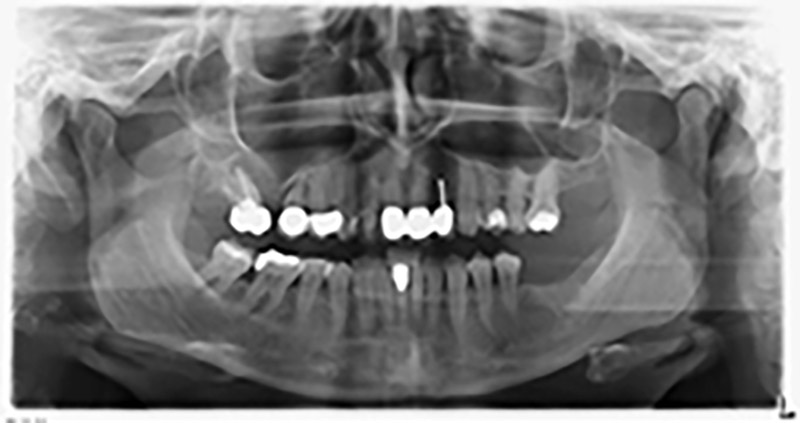

The 59-year-old patient presented with an advanced case of periodontitis, describing an unpleasant feeling and poor taste from the first quadrant in a distal direction. The clinical examination revealed generally enlarged periodontal pockets and very advanced bone atrophy in regions 16 and 14. The radiology confirmed the findings (Fig. 1). Teeth 16 and 14 could not be retained.